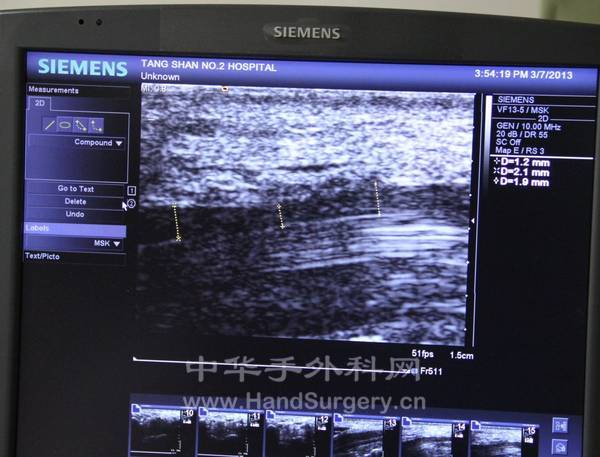

彩超室

主任给我讲解图像显示内容

彩超辅助诊断腕管综合征

正中神经受到腕横韧带卡压

中间变细,D=1.2

两侧变粗,D=1.9,2.1

标记的是正中神经

上边浅层是腕横韧带

下边白色的是屈肌腱